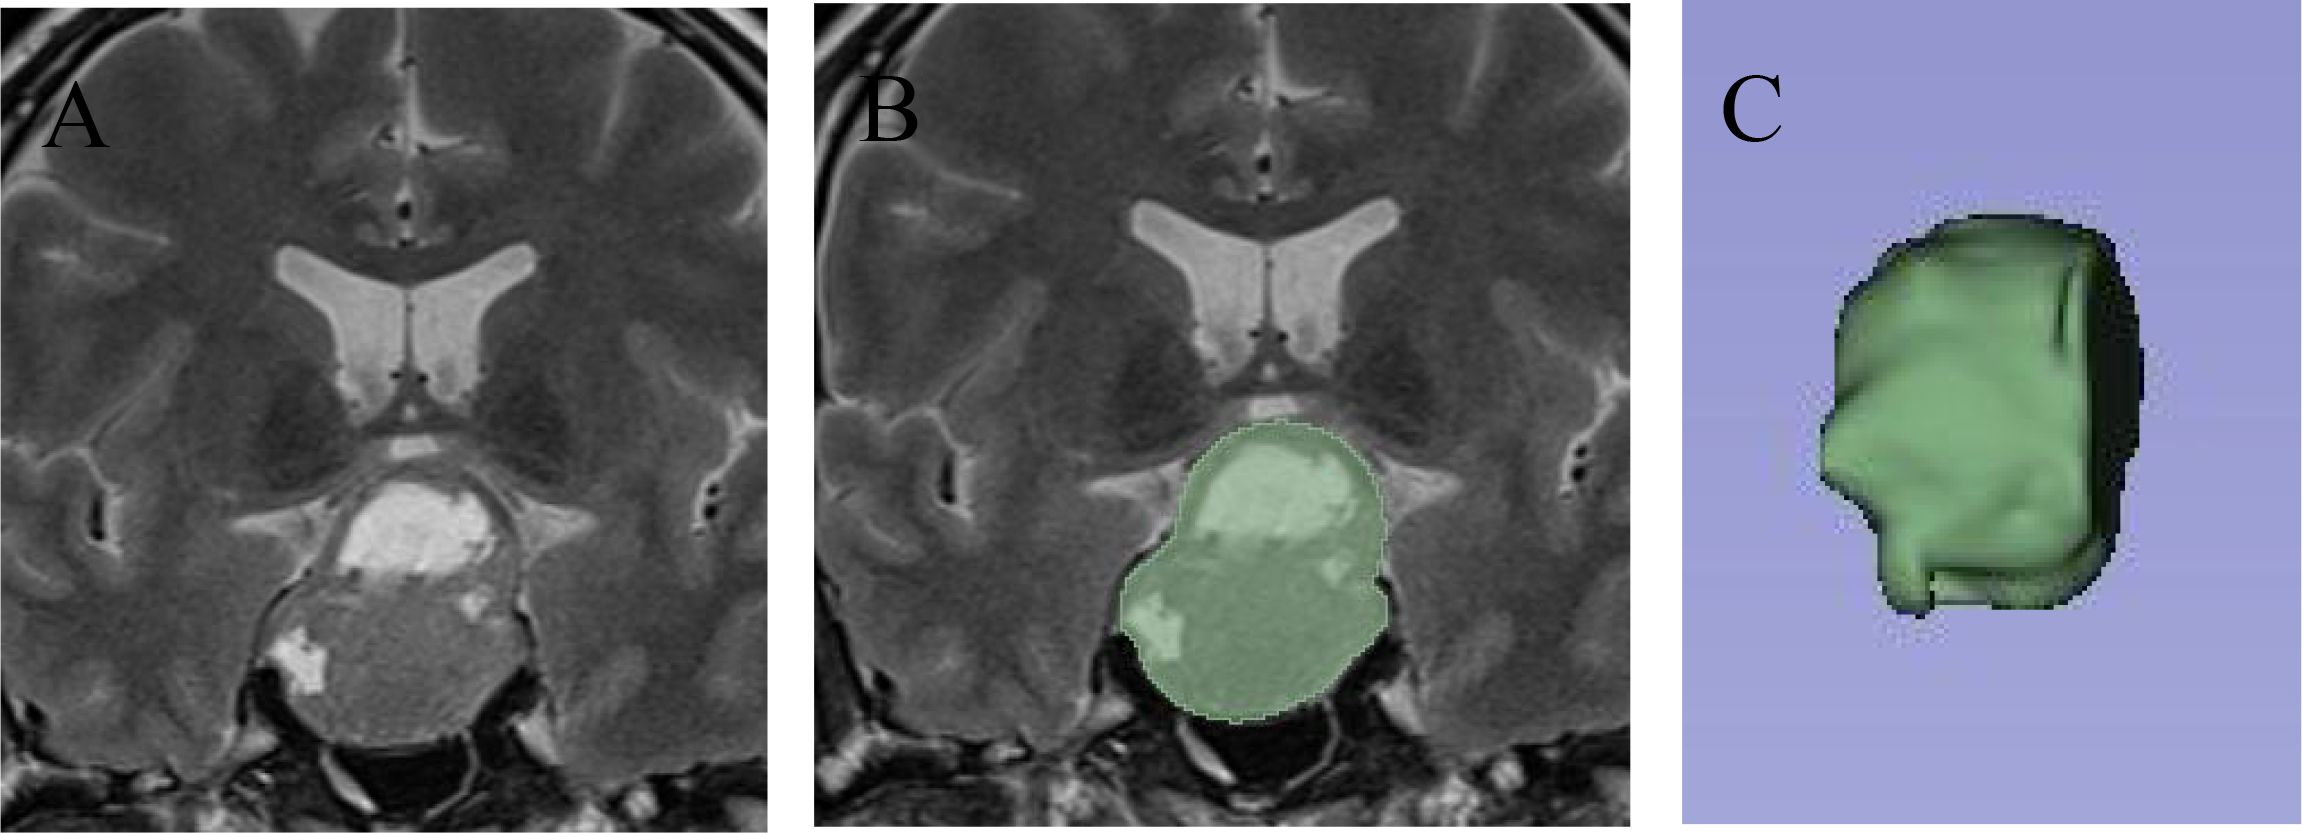

Objective: This study aims to develop a predictive model for cavernous sinus dural invasion in pituitary adenomas by retrospectively analyzing clinical and imaging data. It explores the associations between clinical and radiomics features and cavernous sinus dural invasion. Methods: Clinical data and coronal T2-weighted MRI images were collected from patients diagnosed with pituitary adenomas at our institution between December 2012 and December 2022. Tumor regions of interest (ROIs) were segmented using 3D Slicer, and radiomics features were extracted. Statistically significant radiomics features were identified using Lasso regression and univariate analysis. Clinical features were screened using univariate and multivariate logistic regression analyses. These selected features were incorporated into ten machine learning algorithms to construct three predictive models: a clinical feature model, a radiomics feature model, and a combined clinical and radiomics feature model. Model performance was evaluated to determine the best-performing model, which was further interpreted. Results: A total of 252 patients with histopathologically confirmed pituitary adenomas were included. The analysis identified Knosp grade, tumor left-right diameter, pedunculated satellite tumor, and clival invasion as significant clinical predictors, along with radiomics features including original.4, original.10, log-sigma-5-0-mm-3D.29, log-sigma-5-0-mm-3D.91, wavelet-LLH.37, wavelet-LHL.37, and wavelet-HLL.8. The combined clinical and radiomics model outperformed models based solely on clinical or radiomics features. Among the ten machine learning algorithms, the LightGBM model demonstrated the best predictive performance, achieving an area under the curve (AUC) of 0.86 and an accuracy (ACC) of 0.76. Conclusions: A machine learning model integrating clinical and radiomics features can effectively predict cavernous sinus dural invasion in pituitary adenomas preoperatively, providing a reliable basis for diagnosing tumor invasiveness and developing surgical plans. The LightGBM algorithm exhibited the highest predictive efficacy. Furthermore, the pedunculated satellite tumor feature emerged as a novel imaging marker for cavernous sinus dural invasion, offering new insights into the study of invasive pituitary adenomas.